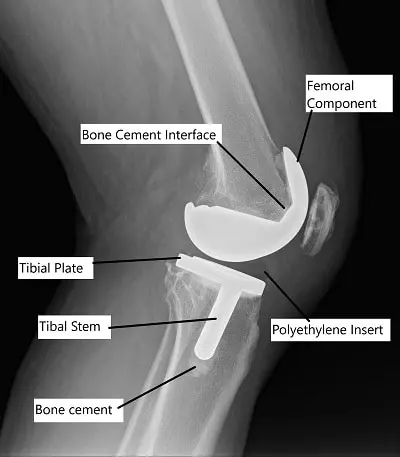

- Cemented Total Knee Replacement: Prosthetic components are fixed to the bone using bone cement. This method is most commonly used and offers immediate stability.

After thoroughly washing the cut segments, acrylic bone cement is applied to the implants and the bone segments. The implants are then fixed to the prepared bed on the bone.

A plastic high-quality polyethylene space is attached to the tibial component to reduce friction between the implants. The acrylic cement hardens quickly providing immediate fixation.